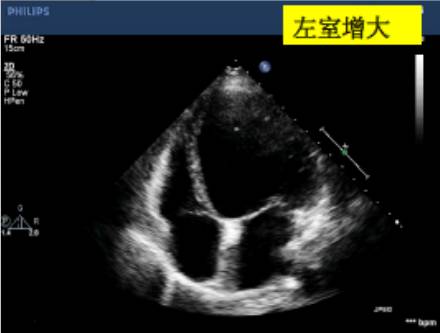

左心室正常值范围——

可用目测方法对定量数据进行反复核查。